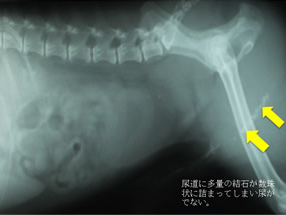

結石破砕システムを使うと尿道に詰まった石を砕き回収することができる。 経尿道的結石破砕術:TULと体外衝撃波破石術:ESWLの2つの治療法があります。当院で行っているのはTULになります。ESWLは小型犬には適応が難しく動物医療では行っているところはありません。TULも当院が日本で初めておこなう高度先進医療です。

TULは全身麻酔をかけて、尿道から尿管鏡という細いファイバー内視鏡を入れて、結石をレーザーや衝撃波で砕き、尿道から取り出す内視鏡手術のことをいいます。結石を尿道から体外に排出することができるので非常に低侵襲な内視鏡手術となります。体の大きさなど条件が必要ですが尿管結石や腎臓結石、胆石も破砕回収が可能です。

他院からの紹介:結石が詰まってチョロチョロしか尿が でずカテーテルも通らない。